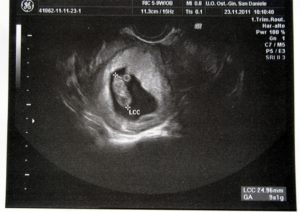

Ультразвуковое исследование на маленьком сроке беременности проводится при помощи специального небольшого датчика, который вводится во влагалище женщины и позволяет медицинскому специалисту детально осмотреть крохотный зародыш.

Зачастую, на данном сроке еще не время проводить УЗИ, однако для подтверждения беременности и оценки ее развития женщина может пройти эту процедуру. У вас беременность 5 недель, фото эмбриона делать еще рано, но уже можно увидеть этот маленький С-образный зародыш.

На сроке 5 недель беременности фото УЗИ покажет, какое количество плодов развивается в материнском чреве, доктор оценит состояние матки.

Можно увидеть в 5 недель беременности фото, где именно в матке закрепились эмбрионы. На УЗИ, когда подходит к концу пятая неделя беременности, фото малыша делать действительно рано, зато уже можно услышать сердце вашего малютки, и увидеть, как оно стучит!

Обычно ультразвуковое исследование на 5 неделе делают с целью подтвердить случившуюся беременность. Поскольку зародыш еще совсем маленький, то ультразвуковая диагностика проводится трансвагинальным способом, т. е.

специальный датчик вводится во влагалище. Подобная методика позволяет более детально обследовать зародыш.